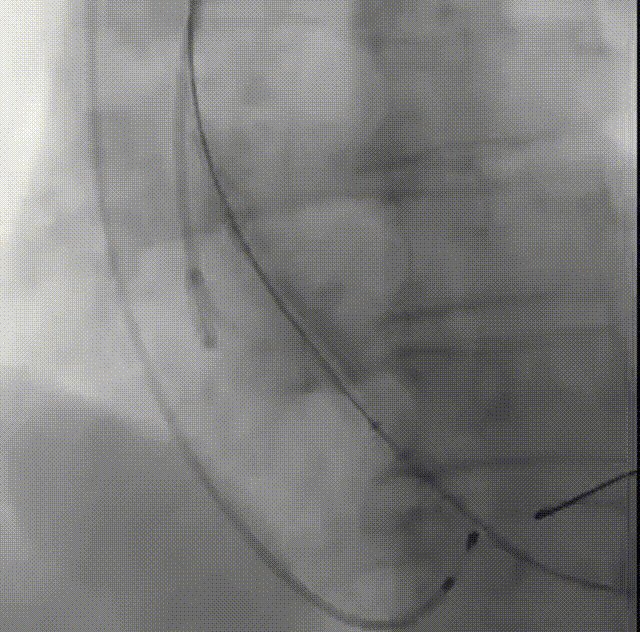

罗建方教授 广东省人民医院(点击查看专家详细简历) 设计本为临床需,耐久守护好芳华:任何医疗产品的设计初衷与最终归宿,都应落在 “临床获益” 这一核心上。尤其在 TAVR 领域,年轻患者预期寿命长,术后瓣膜的长期性能直接关乎其生活质量与生存预后。瓣膜耐久性问题,是落到临床实践中亟待突破的关键课题。传统瓣膜在长期使用中,可能因结构老化、功能退化等问题,难以满足年轻群体数十年的健康需求,二次手术风险也随之攀升。因此,产品设计必须直面这一临床痛点:通过材料革新增强抗钙化性能及生物相容性,以技术突破延长瓣膜有效使用寿命。此次临床应用的预装干瓣Prostyle A®是TAVR领域的革新理念,干瓣预期会为临床提供更耐久性的保障,实现了与临床需求的精准对接,为年轻群体的瓣膜治疗提供更坚实的保障。 李捷教授 广东省人民医院(点击查看专家详细简历) 干瓣技术求革新,性能兼顾护临床:干瓣的技术革新在创新的同时需要和临床实际需求深度耦合,兼顾TAVR术中的核心考量点。临床操作中,瓣膜能否顺利过弓,直接影响手术效率与安全性。Prostyle A®短瓣架设计及第二台阶的柔顺设计,术中操作丝滑;同时,瓣膜植入后的径向支撑力必须平衡得当,才能实现稳定锚定;释放后造影显示:瓣膜形态舒展,轻度瓣周漏,舒张压升高,冠脉开口未受影响;瓣周漏是影响术后效果的关键隐患,双层裙边设计通过多重密封机制降低反流风险,为患者长期获益筑牢防线。这些性能的协同优化,最终目的是让干瓣在临床中真正做到 “好用、耐用、安全用”,为患者预后提升提供坚实支撑。 患者病史 患者因 “活动后气促伴头晕 2 月” 入院。 现病史:2月前无诱因出现活动后气促,休息后缓解,伴头晕,夜间阵发性呼吸困难。超声检查发现:主动脉瓣重度狭窄并重度返流(跨瓣流速 4.3m/s,峰值压差 73mmHg);主动脉 + 冠状动脉 CTA 提示主动脉瓣显著钙化,升主动脉及分支粥样硬化,冠状动脉轻度狭窄(RCA 狭窄 30-40%)。 既往史:高血压病史 15 年,规律服药,血压控制稳定。 术前诊断:非风湿性主动脉瓣狭窄伴关闭不全(重度)、心功能 II 级(NYHA)、高血压病 2 级(高危)、冠状动脉粥样硬化。 术前CT 三叶瓣,瓣叶增厚中度钙化,右无交界钙化粘连,瓣环径25.1mm,LVOT 25.1mm,直筒型结构;窦部空间足够,升主未见增宽,瓣环水平夹角55°;冠脉开口位置佳,无冠脉风险;入路散在钙化、外周双侧入路无明显迂曲,双侧内径可、中分叉,左右侧均能够支持20F 大鞘通过。 造影角度及入路 手术策略 右侧股动脉为主入路,左侧为辅助入路;使用20球囊预扩,准备AV26瓣膜,冲洗口朝向3点钟方向送入输送系统性能,初始定位真实瓣环0位释放,最终锚定约瓣下3mm,工作位评估瓣膜稳定性与冠脉情况。 手术过程 根部造影 20mm 球囊预扩无明显腰征 术中使用26号瓣膜,瓣膜释放贴边迅速 80% 工作位观察瓣膜位置良好 释放后造影显示:瓣膜形态舒展,轻度瓣周漏,舒张压由术前30mmHg升为 60mmHg,冠脉开口未受影响。 术后超声:跨瓣流速降至1.6m/s,平均压差降至5 mmHg,心功能显著改善。 Prostyle A®预装干瓣——助力临床最优化解决方案: 1. 抗钙化与耐久性:Micro-EX™专利技术提升瓣膜抗钙化能力,适配患者瓣叶中度钙化的解剖特点,为长期疗效提供保障。 2. 柔顺过弓与精准定位:短瓣架设计 + 远端超滑涂层,确保患者输送系统过弓顺畅;瓣架流入端微直筒设计,让定位贴边更迅速,减少了手术时间; 3. 80% 可回收设计:便于术中调整观察,减少起搏时间,从而减少并发症。 4. 简化手术流程:预装设计缩短操作时间,20F 大鞘兼容外周入路,降低血管损伤风险。 · END ·